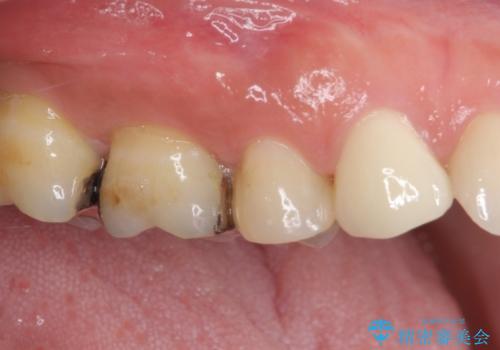

- 奥歯に痛みを感じるようになり、更にはその前の歯のセラミックが欠けてしまったとのことで来院された患者様です。

痛みがしばらく続いていたため、抜髄となる可能性を考慮しながら処置を行うこととしました。

処置後に痛みの状態を確認し、前歯のクラウンの再製作を同時に進めることとしました。

銀歯の下の虫歯はそれほど大きくなく、初回の処置以降、痛みを感じることはなくなりました。

セラミックインレー装着後も痛みが生じることはなく、神経の状態も正常な反応が認められました。